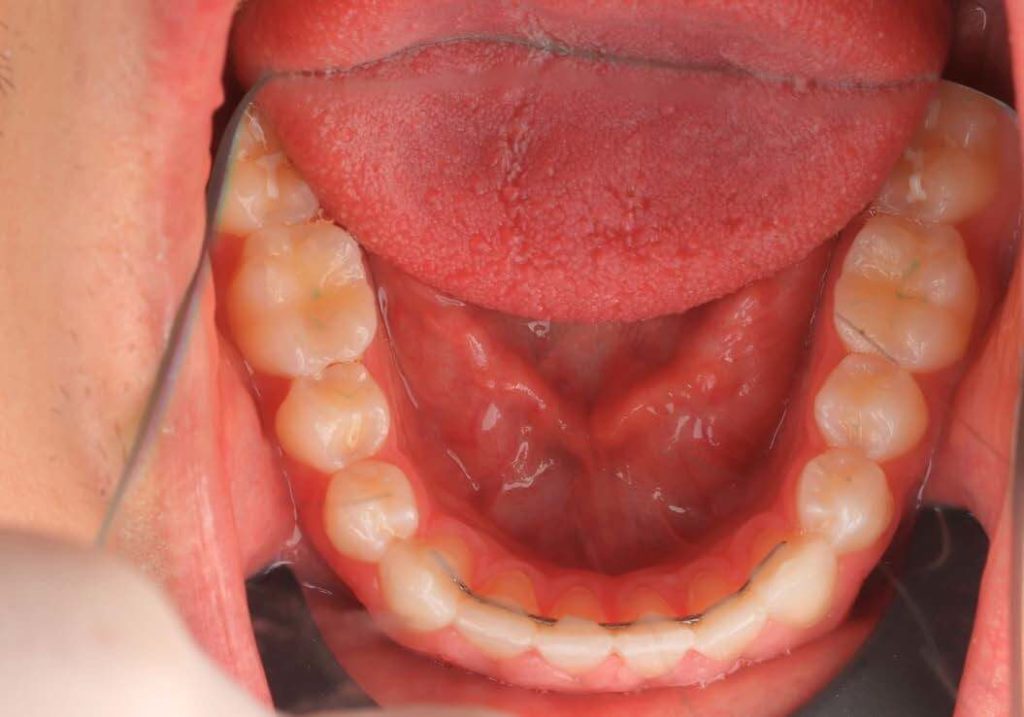

SITUACIÓN INICIAL

CLASE I MORDIDA CRUZADA EN LATERALES

• Clase I con mordida cruzada en los incisivos laterales.

• Apiñamiento moderado en el arco superior e inferior.